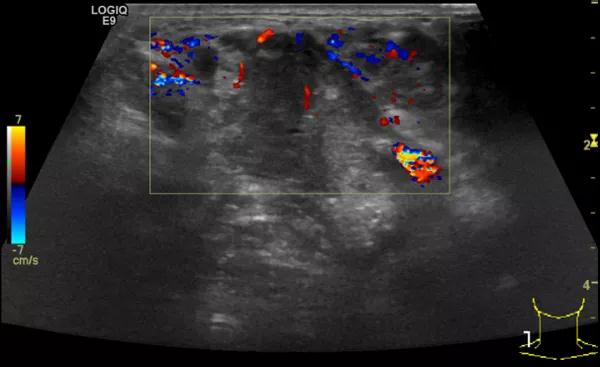

第二例是食管癌患者,术后半年余锁骨上固定淋巴结可触及肿大,疼痛非常明显,系统治疗后无缓解,患者希望通过局部处理缓解症状。造影显示强化信号明显,结节部分区域坏死,故主要针对强化区域从后向前的逐层的消融,皮下进行液体隔离减少烫伤。热消融后影像显示血流增强消失,弹性、硬度增高,一个月后复查显示充盈缺损,完全消融,疗效远超预期。

(病例2图例)